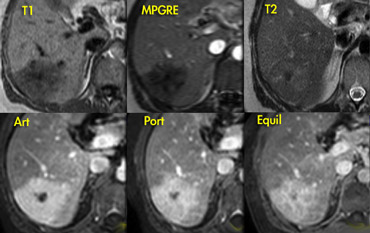

Hemangioma and FNH on ultrasound and dynamic MR. Hemangioma and FNH on ultrasound and dynamic MR.

Focal Nodular Hyperplasia (4)

The ultrasound image on the left shows two lesions.

The small one (blue arrow) is characteristic of a hemangioma, while the larger one (green arrow) is non specific on US.

On T2WI the hemangioma shows the typical homogeneous hyperintensity .

The larger lesion is somewhat hypointense on T1 and somewhat hyperintense on T2.

The enhancement is almost homogeneous with small septae that do not enhance in the arterial phase and do show late enhancement (yellow arrows).

The enhancement is almost homogeneous with small septae that do not enhance in the arterial phase, and do show late enhancement (yellow arrows).

We also characterize this lesion as FNH.